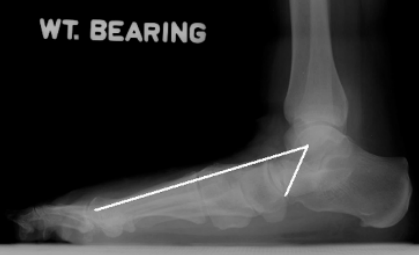

13 后足—跟骨倾斜角

跟骨倾斜角calcaneal pitch angle/heel pitch angle,HPA/calcaneal inclination:负重侧位片中跟骨下表面最低两点连线与水平线的夹角

正常范围:10~30°。对足弓判断较为敏感,特异性也较高<10°平足,>30°弓形足